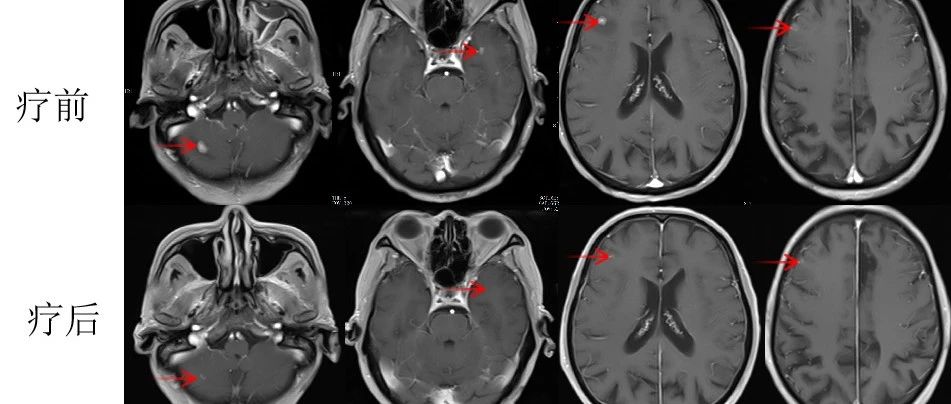

張老太,70歲, 2024年8月因頭暈頭痛,頻繁嘔吐等癥狀入院。頭部磁共振檢查顯示,顱內(nèi)多發(fā)腦轉(zhuǎn)移瘤病灶(見圖)。同時(shí),患者胸部CT檢查可見肺內(nèi)多發(fā)較大腫瘤病灶(見圖)?;颊哂?024年8月20日行CT引導(dǎo)肺腫物穿刺活檢。病理診斷為肺腺癌。綜合診斷為肺腺癌IVB期,腦、肺內(nèi)、右腎上腺多發(fā)轉(zhuǎn)移?;颊哌M(jìn)一步行腫瘤組織基因檢測(cè)和免疫檢查點(diǎn)分子——細(xì)胞程序性死亡配體1(PDL1)檢測(cè)。

圖注:磁共振檢查,小腦蚓部、右側(cè)基底節(jié)-放射冠異常信號(hào)影,考慮轉(zhuǎn)移瘤,伴灶周水腫。

患者于2024年08月20開始接受頭部放療。采用最新一代智慧化精準(zhǔn)放療系統(tǒng)——Halcyon“速銳刀”,成功控制患者全部顱內(nèi)病灶,過程順利,沒有明顯副反應(yīng)發(fā)生。患者基因檢測(cè)結(jié)果為陰性,沒有找到具有靶向治療藥物的突變基因。此外,患者年齡較大,體質(zhì)較弱,全身多發(fā)轉(zhuǎn)移病灶,為治療帶來了巨大的挑戰(zhàn)。然而,患者PDL1檢測(cè)顯示,PDL1高表達(dá)(PD-L1 TPS=98%),提示免疫治療有效率較高。潘振宇教授團(tuán)隊(duì)為患者制定了個(gè)體化精準(zhǔn)腫瘤治療方案,僅僅每3周應(yīng)用1次免疫治療藥物。經(jīng)過3次治療后復(fù)查,患者肺內(nèi)病灶顯著縮退,顱內(nèi)病灶縮退。治療過程中,僅出現(xiàn)一過性皮疹。目前患者恢復(fù)良好,生活完全自理。

圖注:治療后復(fù)查磁共振顯示,顱內(nèi)病灶明顯縮小。

林老先生,67歲,患者2024年8月因咳嗽、咳痰,并發(fā)現(xiàn)頸部包塊入院。入院后經(jīng)CT檢查發(fā)現(xiàn),肺內(nèi)及頸部可見多發(fā)腫瘤病灶(見圖)。于2024年8月21日行超聲引導(dǎo)下頸部淋巴結(jié)穿刺活檢術(shù)。術(shù)后病理提示:右頸轉(zhuǎn)移性肺腺癌。頭部磁共振檢查顯示,顱內(nèi)多發(fā)腦轉(zhuǎn)移瘤病灶(見圖)。診斷為肺腺癌,腦、頸部淋巴結(jié)、肺內(nèi)多發(fā)轉(zhuǎn)移IVB期。進(jìn)一步對(duì)患者腫瘤組織進(jìn)行腫瘤組織基因檢測(cè)和免疫檢查點(diǎn)分子——細(xì)胞程序性死亡配體1(PDL1)檢測(cè)。

圖注:磁共振檢查,顱內(nèi)多發(fā)腦轉(zhuǎn)移瘤病灶。

患者基因檢測(cè)結(jié)果為陰性,沒有找到具有靶向治療藥物的突變基因。此外,患者年齡較大,體質(zhì)非常瘦弱,全身多發(fā)轉(zhuǎn)移病灶,為治療帶來了巨大的挑戰(zhàn)。然而,患者PDL1檢測(cè)顯示,PDL1高表達(dá)(PD-L1患者TPS98% CPS100%),提示免疫治療有效率較高。潘振宇教授團(tuán)隊(duì)為患者制定了個(gè)體化精準(zhǔn)腫瘤治療方案,患者于2024年9月21日開始接受頭部放療。采用最新一代智慧化精準(zhǔn)放療系統(tǒng)——Halcyon“速銳刀”,成功控制患者全部顱內(nèi)病灶。治療過程順利,沒有副反應(yīng)發(fā)生。隨后,給予患者每3周1次免疫治療。經(jīng)過3次免疫治療后復(fù)查,患者肺內(nèi)病灶顯著縮退,癥狀明顯恢復(fù),沒有明顯副反應(yīng)發(fā)生。目前狀態(tài)恢復(fù)良好,生活完全自理。

圖注:治療后復(fù)查磁共振顯示,T1增強(qiáng)掃描可見顱內(nèi)強(qiáng)化轉(zhuǎn)移病灶較前明顯縮退,部分消失。